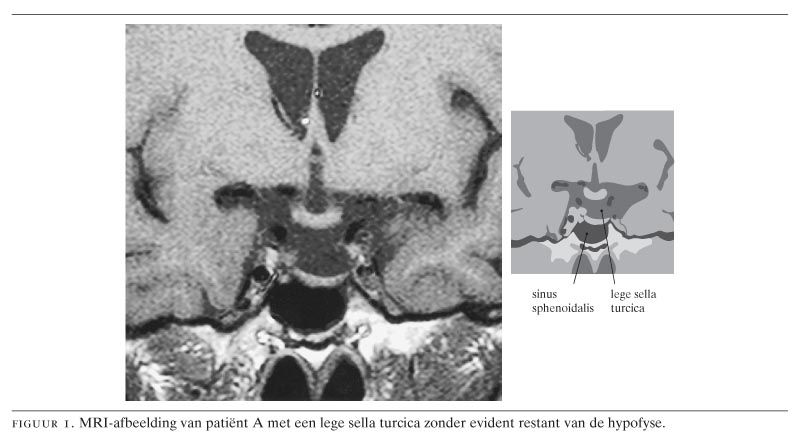

Bij 2 patiënten, mannen van 78 en 42 jaar, werd een lege sella turcica (‘empty sella syndrome’) aangetroffen. De eerste patiënt kwam met chronische vermoeidheid, bij de tweede was de lege sella ontstaan als laattijdig gevolg van een eerdere neurochirurgische ingreep, die gevolgd was door uitwendige bestraling. Beiden hadden panhypopituïtarisme. De diagnose werd gesteld met behulp van laboratoriumtests en MRI-onderzoek. Adequate behandeling bestond uit hormoonsuppletie. Het beloop van het empty-sellasyndroom is meestal goedaardig en met adequate suppletie van deficiënte hormonen wordt een goede kwaliteit van leven gehandhaafd.